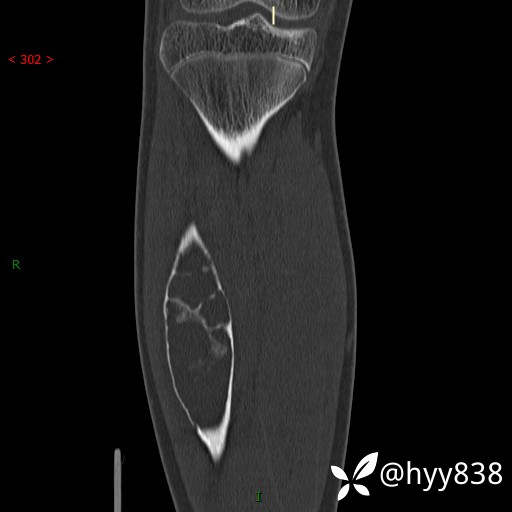

CT MPR COR